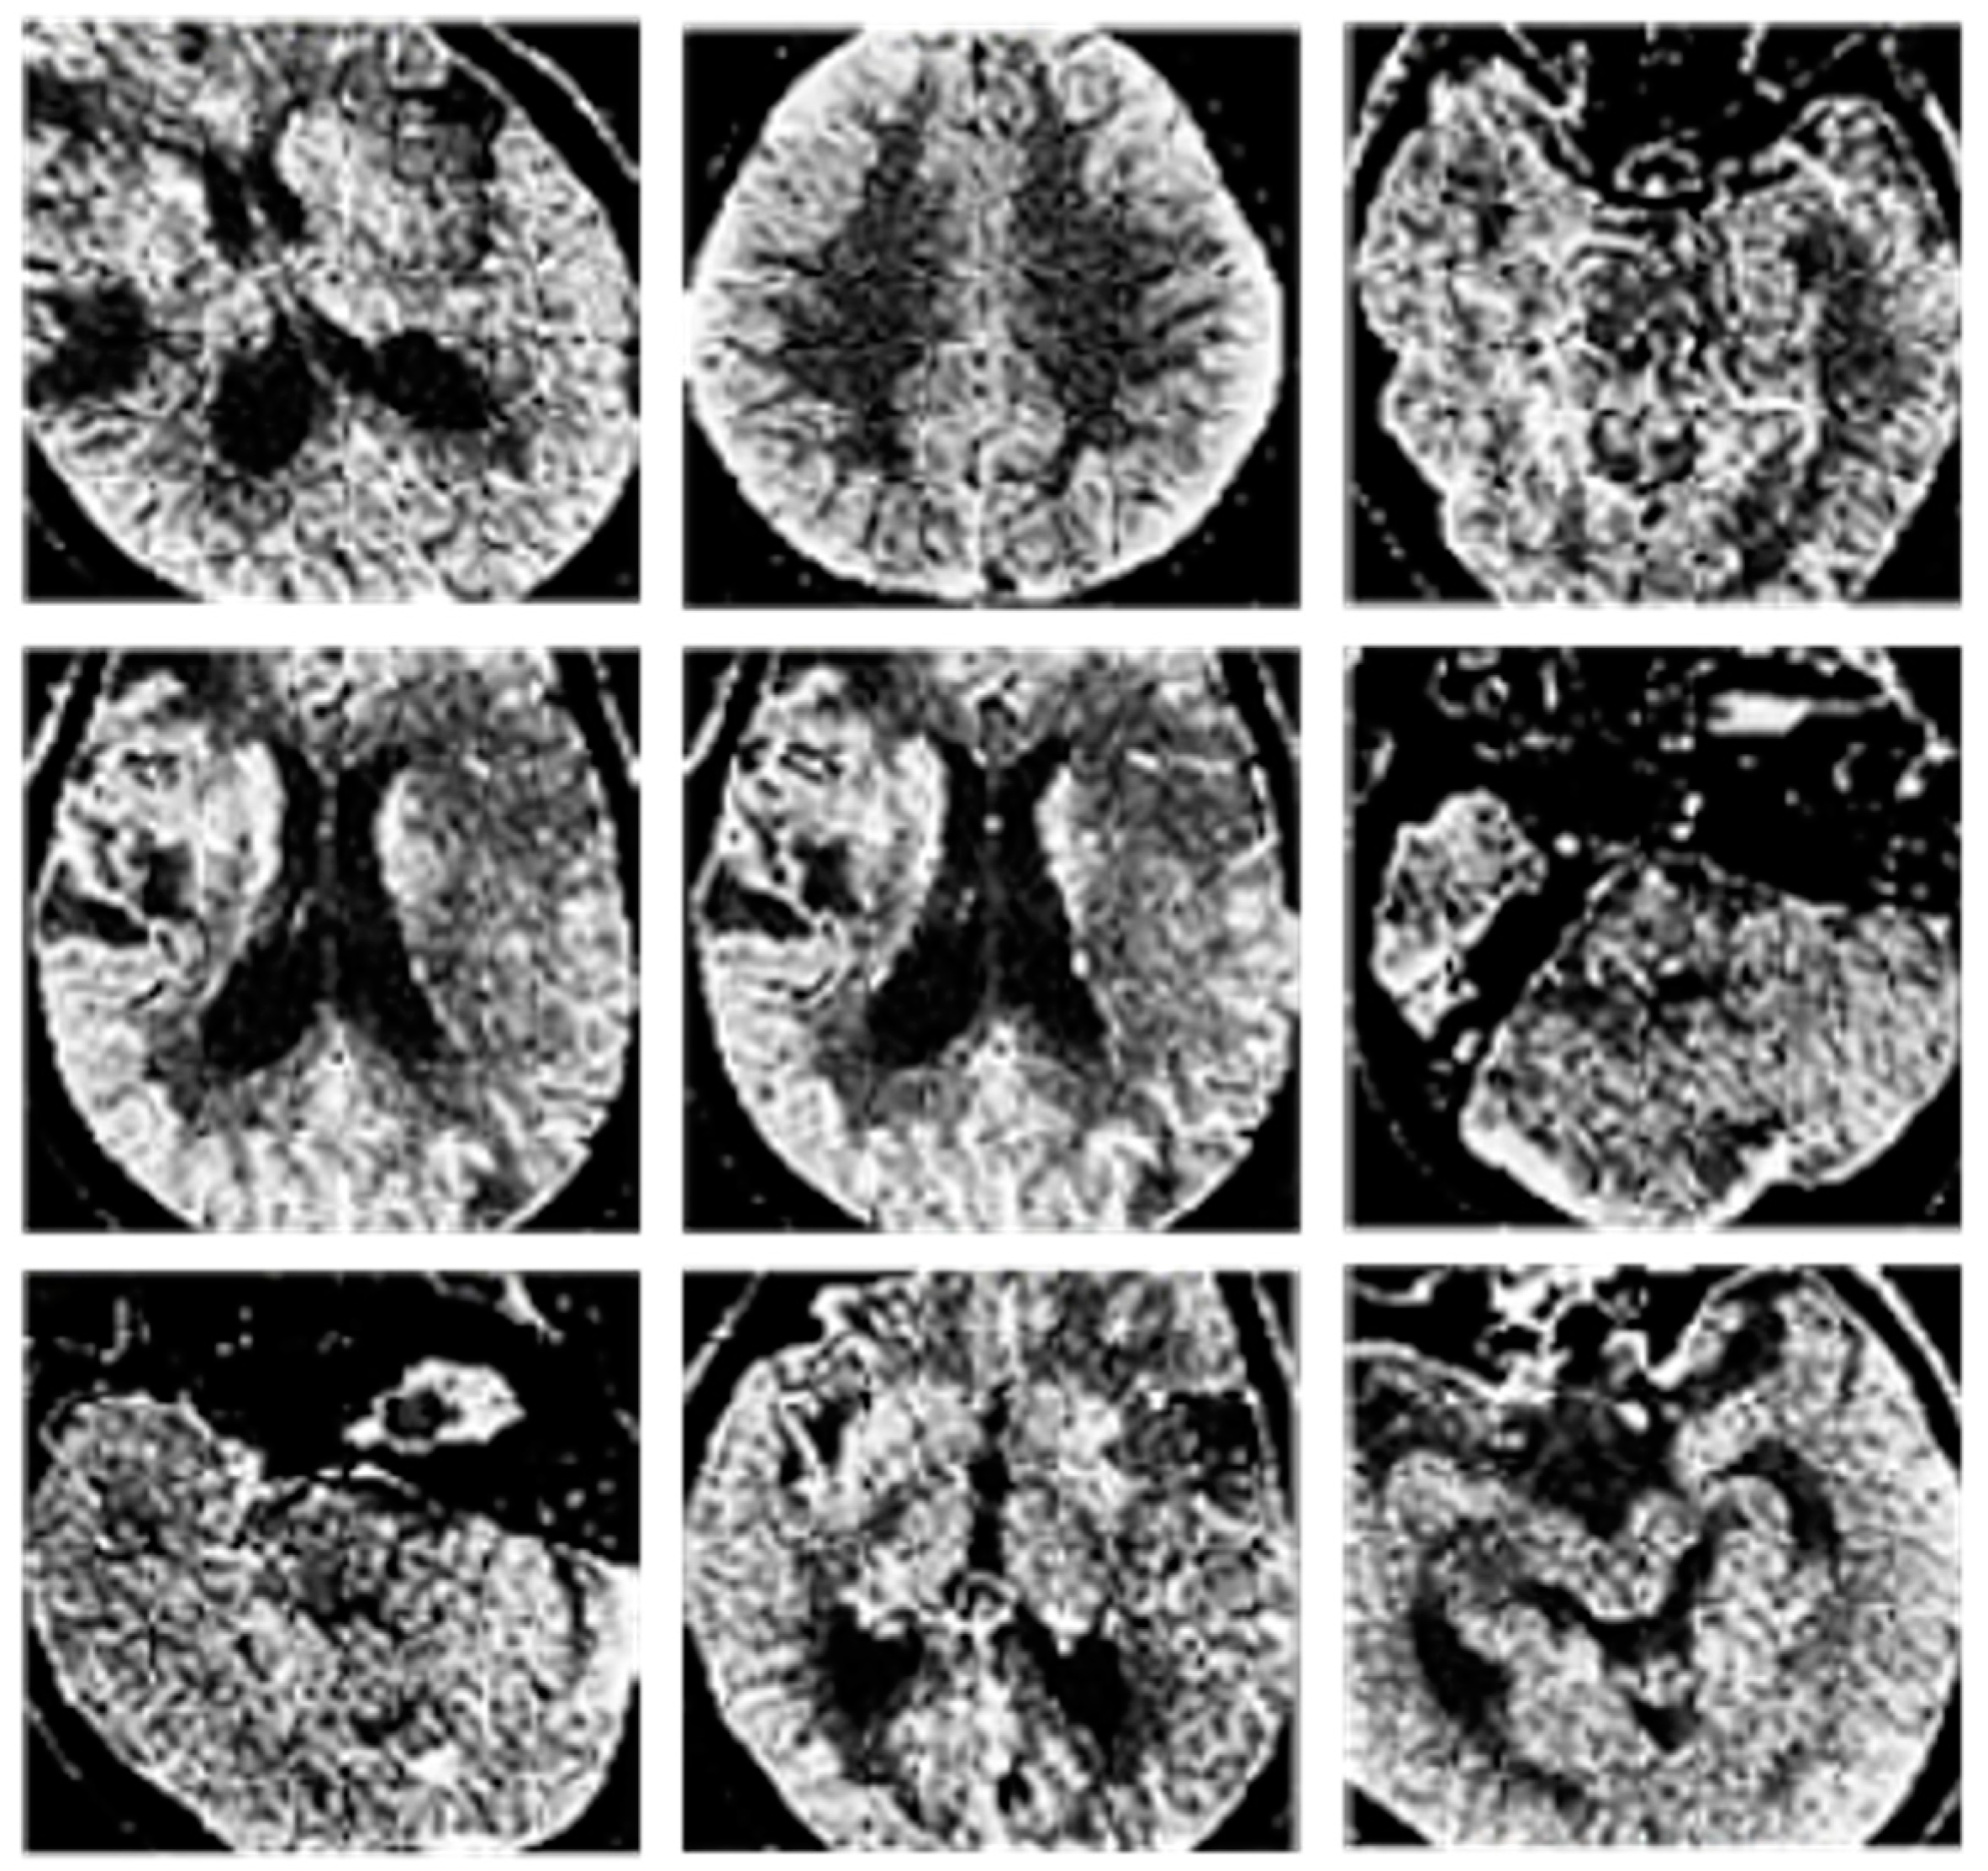

Examples of the classification results are provided in Figure 5 and Figure 6.

Figure 5. Results of CT image classification. In particular, CT images with artifacts.

Figure 6. Results of CT image classification. In particular, CT images without artifacts.